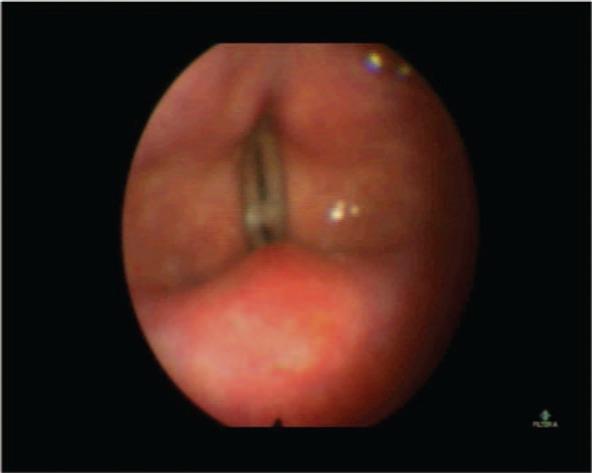

Microlaryngoscopy for benign vocal cord lesion excision is a procedure with good outcomes and relatively few complications that is performed worldwide. The anterior one-third of the vocal cords is a relatively common site to find benign polyps, and the excision of cases with adequate laryngeal exposure is relatively easy. However, they can sometimes present a challenge when laryngeal exposure is suboptimal, which leads to trouble in accessing the site. The factors that can lead to difficulties in laryngeal exposure are numerous, such as restricted mouth opening, limited neck extension, large tongue size, and others. The preoperative prediction of difficult laryngeal exposure (DLE) can be obtained by different scoring and grading systems. We have used the Laryngoscore in this case. However, management options for such cases remain limited. Here, we present a case that was managed using channeled cup forceps under fiberoptic endoscopy with the STRIVE-Hi technique used to administer anesthesia.

用于切除良性声带病变的显微喉镜检查是一种在全球范围内开展的、疗效良好且并发症相对较少的手术。声带前三分之一是发现良性息肉相对常见的部位,对于喉暴露充分的病例,切除相对容易。然而,当喉暴露欠佳时,有时会带来挑战,导致难以到达病变部位。导致喉暴露困难的因素众多,如张口受限、颈部伸展受限、舌体过大等。术前可通过不同的评分和分级系统预测困难喉暴露(DLE)。本病例中我们使用了喉镜评分。然而,此类病例的处理选择仍然有限。在此,我们展示一例在纤维内镜下使用通道杯状钳并采用STRIVE-Hi技术实施麻醉进行处理的病例。